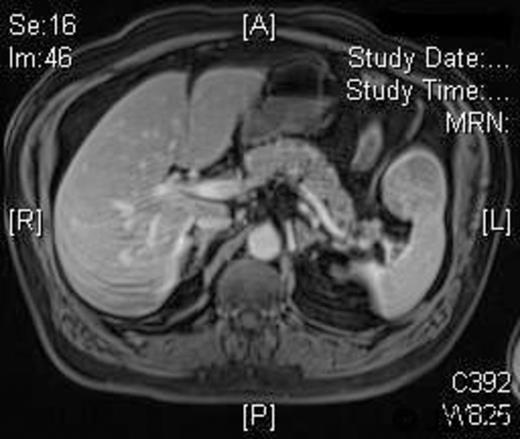

A 58-year-old Caucasian man presented with chest pain, on a background of type-II diabetes mellitus, hypertension and hypercholesterolaemia. A Cardiologist excluded ischaemic heart disease. Full blood count was normal, and an ultrasound scan of the abdomen revealed a 5.5-cm splenic lesion. Computed tomography (CT) revealed a 55mm X 36mm hypodense lesion in the upper pole of the spleen, while magnetic resonance imaging (MRI) demonstrated a well-circumscribed exophytic round mass arising from the anterior aspect of the spleen with features compatible with a benign solid tumour of uncertain malignant potential and multiple liver haemangiomas [Figures 1 and 2]. We proceeded to LPS after the patient had received preoperative vaccinations lest total splenectomy might be necessary.

T1W post-gadolinium MRI: the mass demonstrates a degree of late enhancement